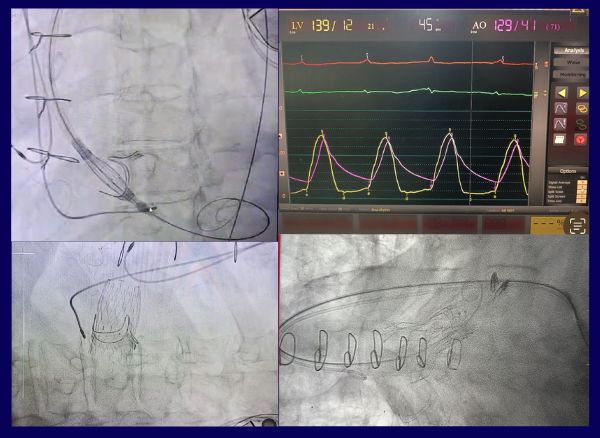

Read MoreTAVI (Transcatheter Aortic Valve Implantation), also known as TAVR (Transcatheter Aortic Valve Replacement), is a revolutionary, minimally invasive procedure used to treat severe aortic stenosis .

MitraClip Success Stories Wockhardt Hospital, Nagpur Central India's first MitraClip procedure! A severe MR case with multiple flail segments, severe LVSD, and a patient on AICD, inotropes, intubation, and chest drain was treated with two clips (XTW & XT). Result: No residual MR, extubated the next day, off inotropes, and LV function improved from 20% to 40%. Kudos to Dr. Nitin Tiwari and team for their outstanding care.

Heavily Calcified AS - hashtag#Edwards S3 ultra - Apollo hashtag#Kolkata Bicuspid AS with horizontal Aorta - hashtag#Abbott Navitor - Apollo hashtag#Kolkata

Read More98 year gentleman with Severe AR due to bioprosthetic valve degeneration (Perimount) with CKD. HRCT used for evaluation on valve sizing and coronary obstruction risk.